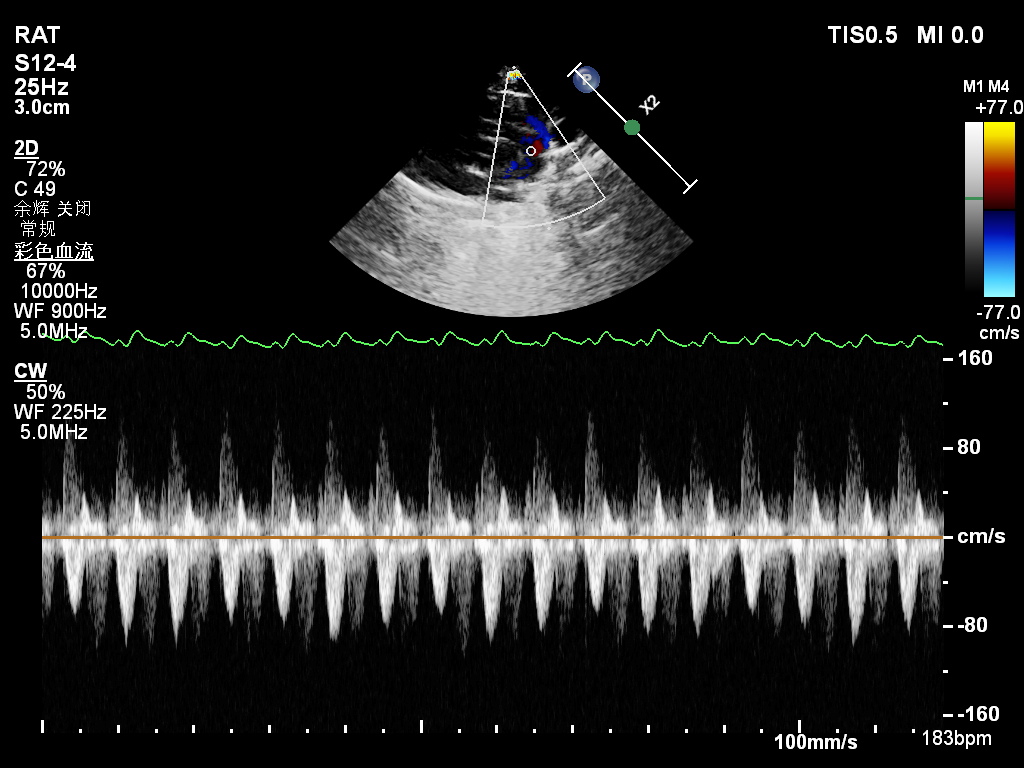

УЗИ сердца у крысы.jpg

УЗИ сердца крысы, задействованной в эксперименте

Фото предоставил аспирант ТГУ Линь Хаожун